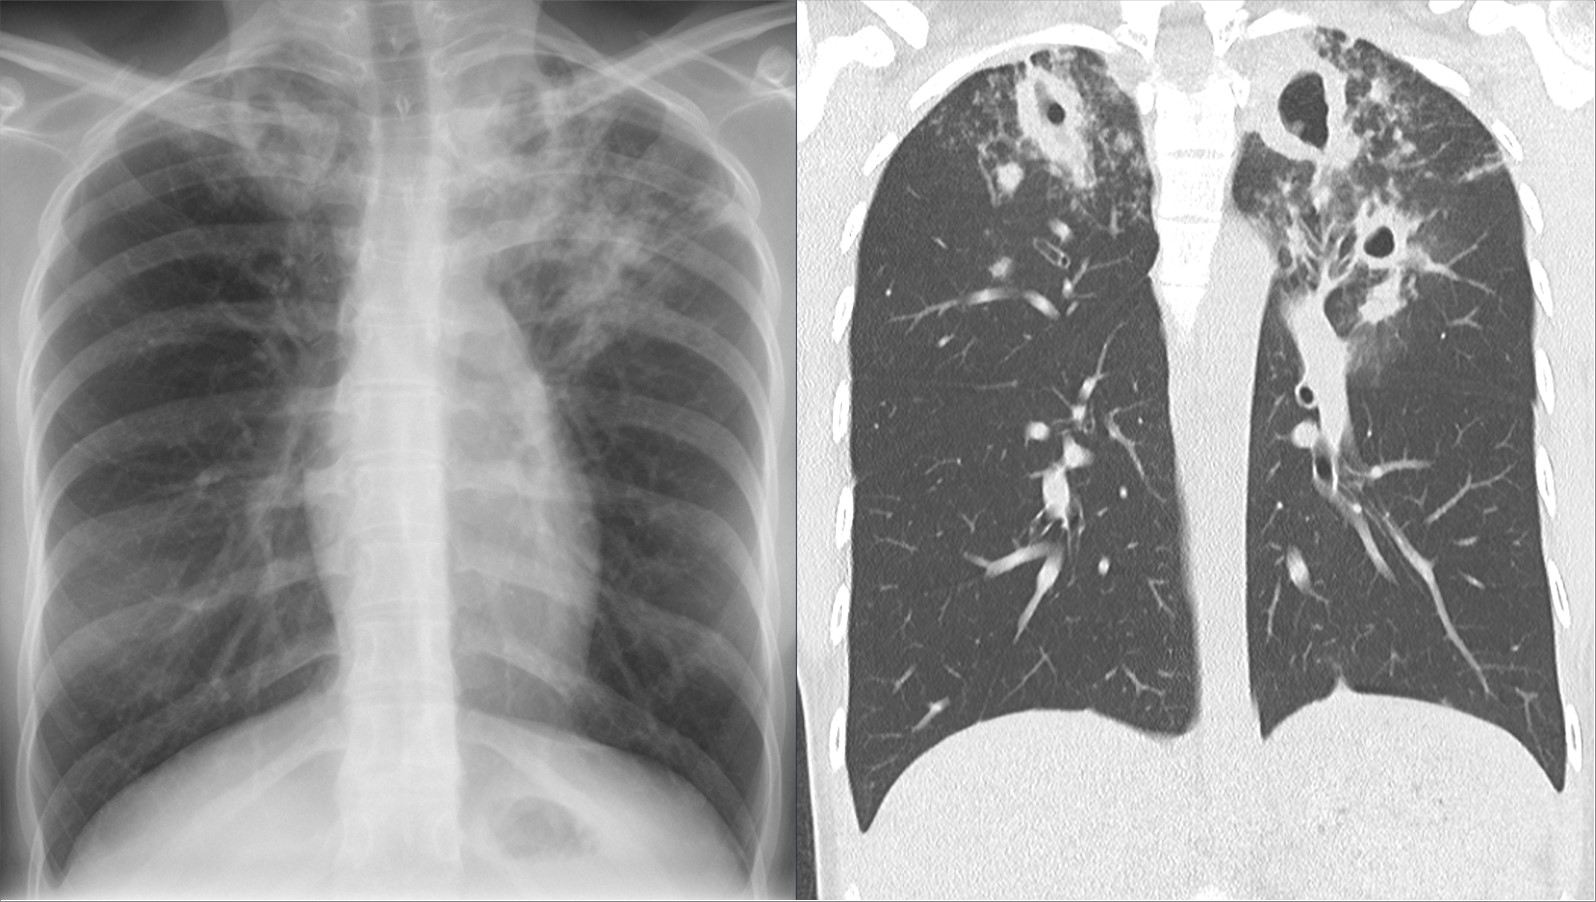

Снимок легких при туберкулезе является важным методом диагностики этого заболевания. На рентгеновских снимках можно увидеть изменения в легких, которые свойственны туберкулезу.

Кт лёгких при туберкулёзе

Инфильтративный туберкулез легких кт

Фотографии снимков легких при туберкулезе

В данной статье представлены многочисленные фотографии снимков легких при туберкулезе, чтобы помочь вам понять, как выглядят изменения легких на рентгеновских снимках при этом заболевании.